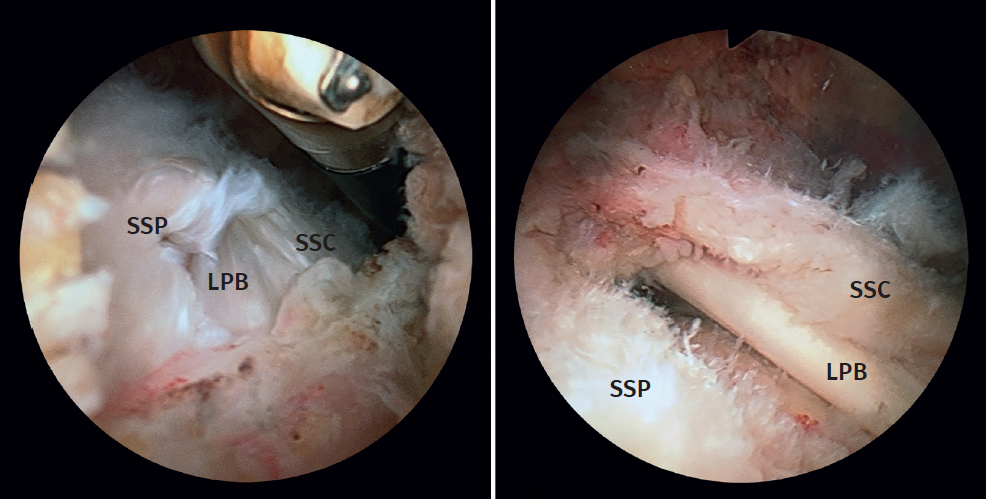

Figure 2. Subclassification of combined and partial ruptures of the subscapularis and supraspinatus into types IA, IB and IIA, IIB.

Arthroscopic exploration allowed combined assessment of the damage to the SSC and anterior margin of the SSP. According to the form of presentation of this association, isolated partial ruptures of the SSC were subclassified as types I-A and II-A, while partial SSC ruptures combined with incomplete ruptures of the most anterior portion of the SSP or AS pattern ruptures were subclassified as types I-B and II-B (Figure 2). This is a personalised subclassification that we feel to be necessary in order to adequately interpret the results of the joint repair of both tendons, which requires an approach differentiated from that used in isolated SSC repair.

Figure 3. View from the posterior subacromial portal of type IB and IIB ruptures in left shoulders. A: type IB; B: type IIB. LPB: long portion of the biceps; SSC: subscapularis; SSP: supraspinatus.

The type I-A and II-A ruptures were repaired from the glenohumeral space via a posterior viewing portal and an AS portal. In type I-B and II-B ruptures, suturing of the lesion was carried out in the same way, but that of the SSP was completed from the subacromial space using a third anterolateral portal (Figure 3). The type I-A ruptures were usually repaired with a single anchoring, while the type I-B, II-A and II-B ruptures typically required two or three.